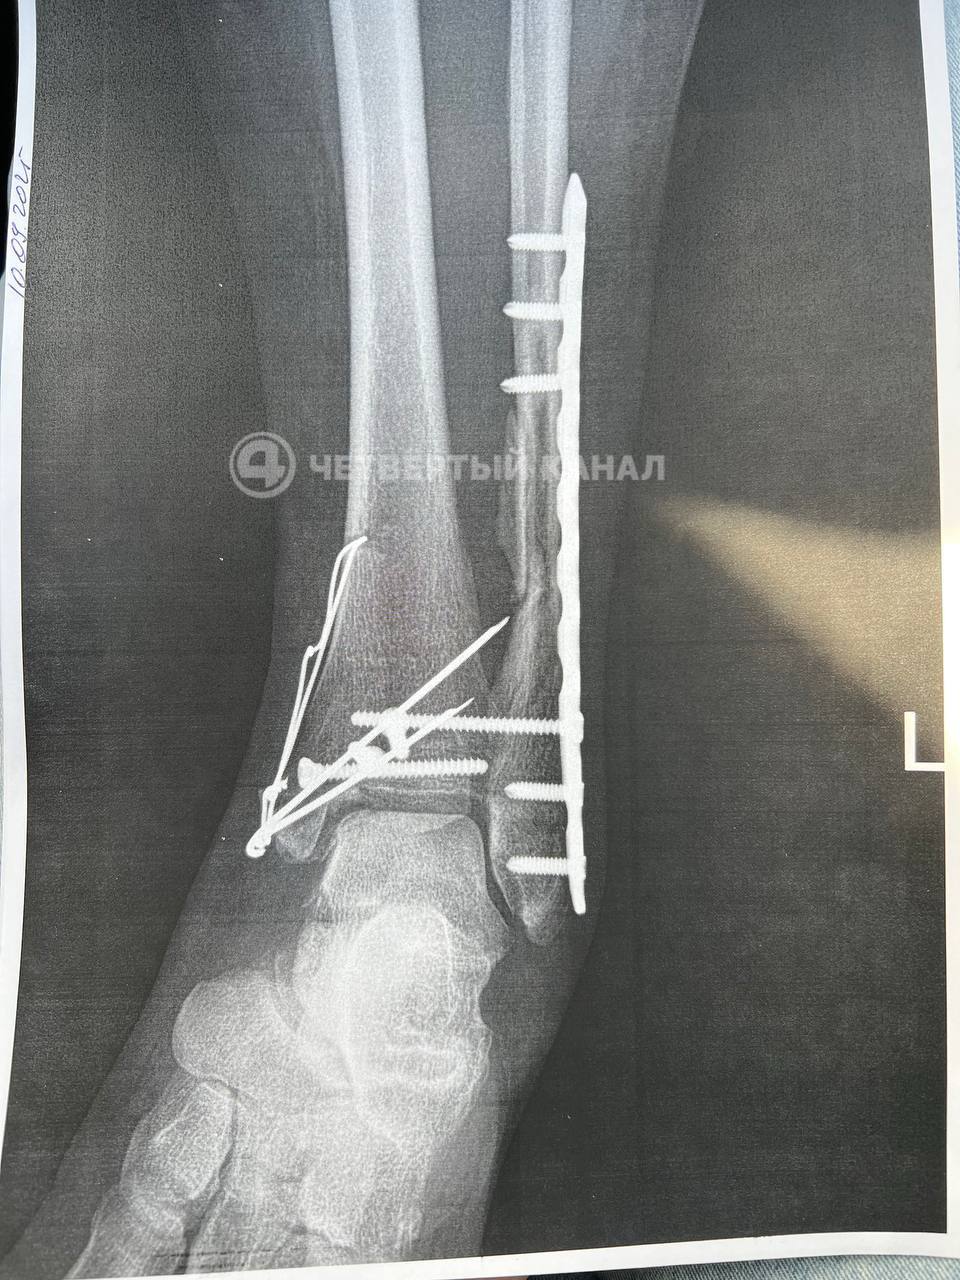

Организатор игры решил попробовать себя роли врача: попытался вправить вывих, но эффекта это не дало — в больнице Марине диагностировали многооскольчатый перелом обеих костей голени, провели операцию: установили 8 болтов и спицу. Экс-владелец клуба считает, что причиной травмы стали индивидуальные особенности строения ног женщины: